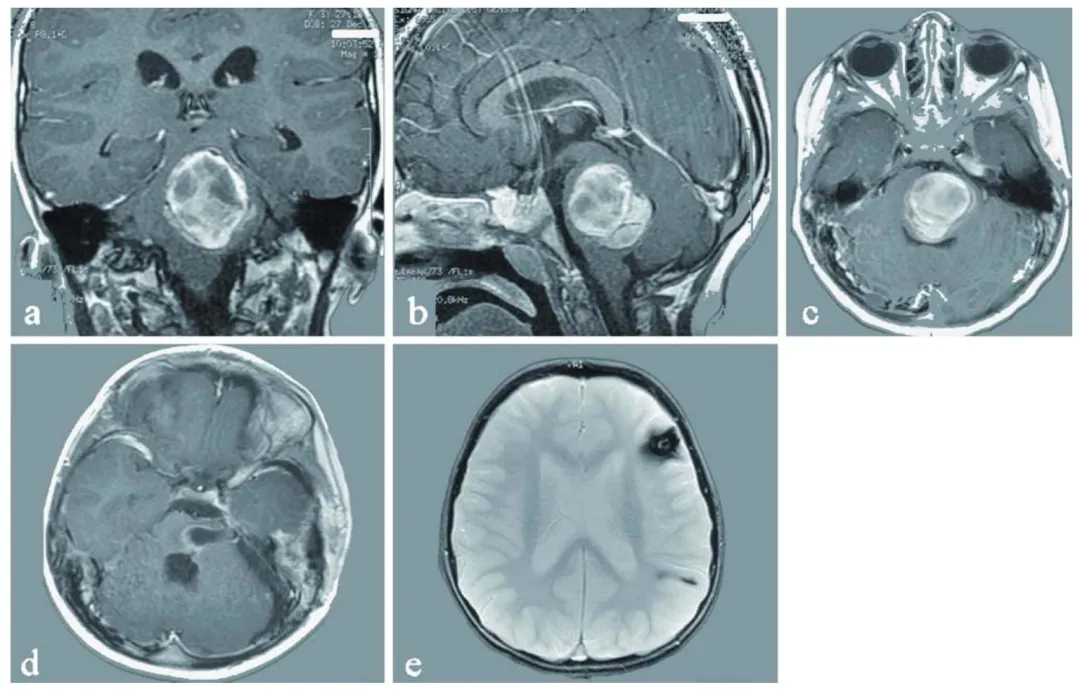

主刀的Rutka教授查房时说,肿瘤已确认实现全切,病理结果显示为...